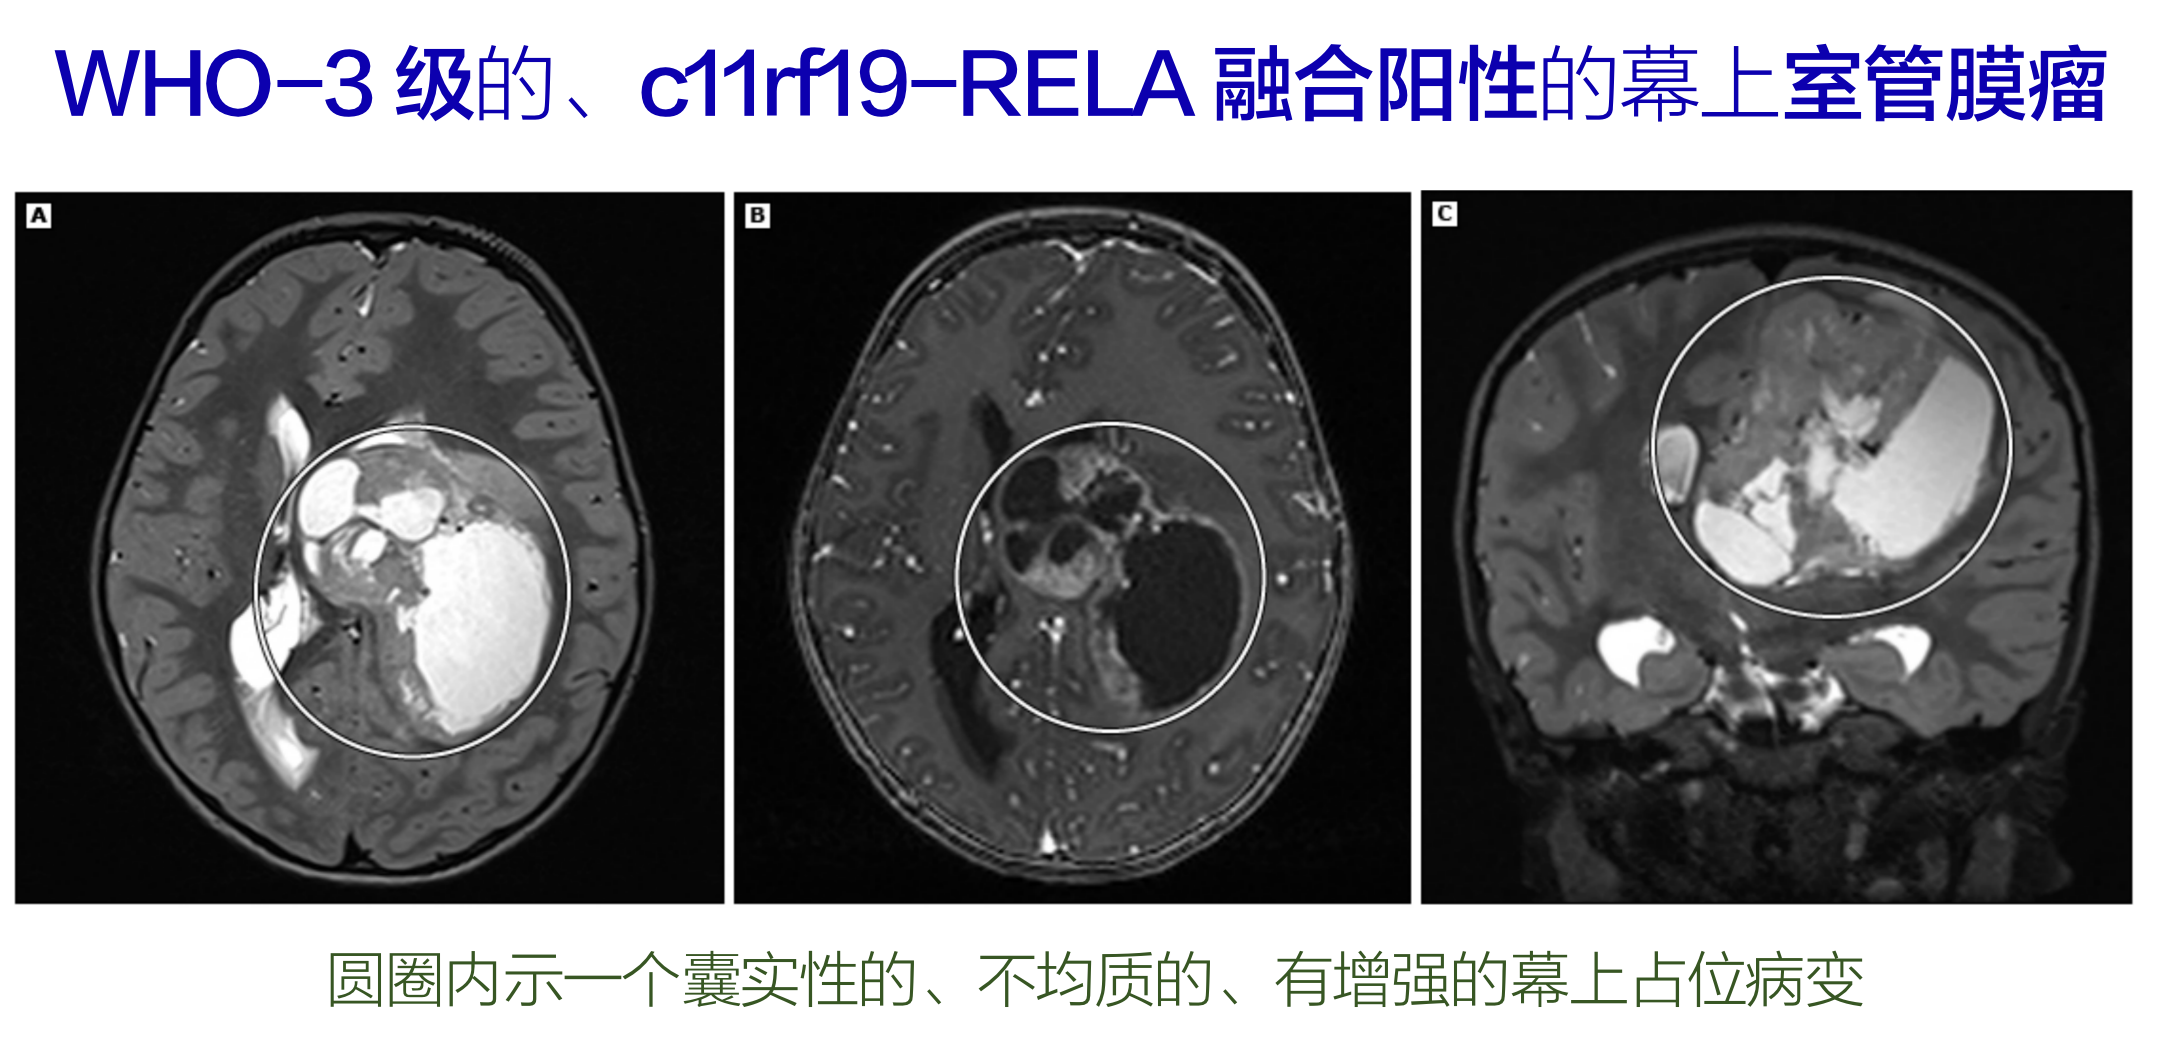

新分类特别列出了两种由分子特征定义的幕上室管膜瘤类型:

①具有ZFTA融合的,这是针对C11orf95的新名称,认为比RELA融合更能代表肿瘤类型,因为它的数量可能比RELA融合更多;

室管膜瘤,在MRI上表现为T1低信号,T2或质子密度像高信号钆增强通常很明显。

肿瘤常侵入第四脑室的外侧孔,从而引起脑积水,但肿瘤周围水肿罕见。在弥散加权成像序列中,室管膜瘤常呈现弥散受限表现。

室管膜瘤在CT上常为高密度均匀强化病灶,囊腔和钙化常见。第四脑室肿瘤内出现钙化强烈提示室管膜瘤,但不具诊断意义。